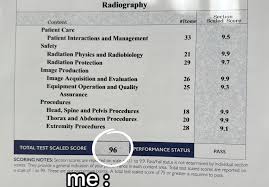

Rad Tech Exam Score PredictionTests, Preparing for the radiologic technologist (rad tech) exam can be stressful, especially when you are unsure how ready you really are. Many students study hard but still feel anxious about their final results. This is …

Rad Tech Exam Full-Length Practice Tests, Preparing for the radiologic technologist certification exam can feel overwhelming. With a wide range of topics, complex imaging concepts, and strict time limits, many students struggle to feel fully confident on exam day. One …